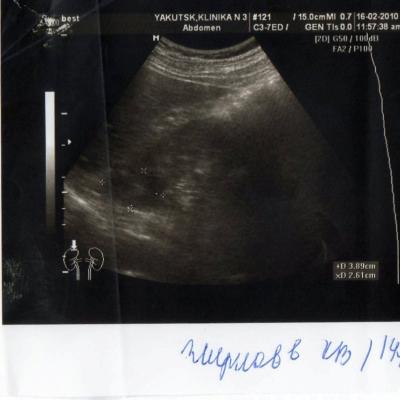

киста почки

2 года назад у меня обнаружили кисту почки. в этом году УЗИ показала,что она исчезла. У меня одна единственная почка размером 146*71, увеличена. Киста размером 2,8*3,8 мм.сейчас почки болят.

Пожалуйста, дайте ответ по рентген фото.